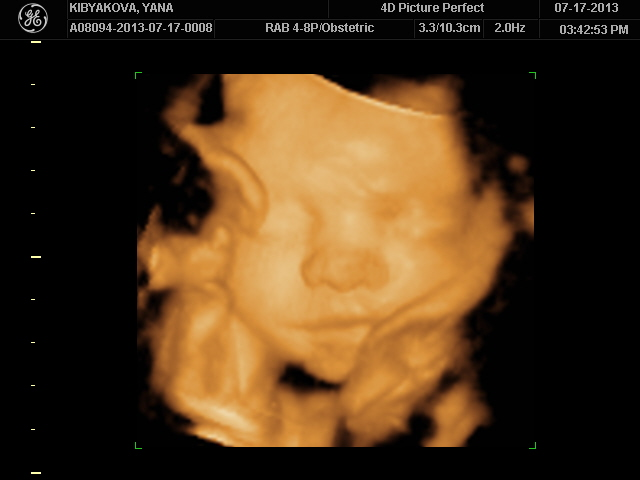

Радовалась я своему капризному мужчине вместо 30 минут - целый час!!!)))Т.к. хорошие снимки он просто не давал сделать!Глазки мы прятали ручками и параллельно запихивали ноги себе в рот! Сына ну зачем ноги то?))))

Чего он только не делал!Там целая фото-сессия получилась у нас из 34 фотографий!

Ноги только уберет,как начинаем снимать в 4Д он их уже тут как тут возле личика держит!)Борьба была серьезная с ним))И пальцы рук в рот пихает или рот вообще открыт - как у папы!)Ноги выше головы - и куда он их так задрал!?Место у него для них ещё есть))Обитает он вниз головой,но строго с правой стороны и где голова там и ноги с руками))

Спорили после с мужем на кого он похож!Мои родители в голос закричали что он моя копия,кроме глаз, муж говорит что нос его и верхняя губа тоже,а нижняя моя!))Я не стала ни с кем спорить просто весь день перекручиваю подробности узи)Моя кроха даже улыбаться умеет и хмуриться - это мы тоже увидели,жаль заснять не успели...В общем я со своих эмоций уже всего и не вспомню, но знаю точно что это было пока что самое лучше свидание с ним!)